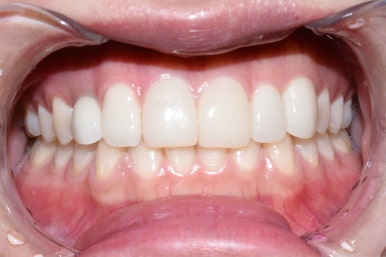

앞니 치료 후

이렇게 1개 임플란트, 2개 라미네이트, 3개 크라운 총 6개 앞니의 치료가 마무리 되었습니다.

6개 모두 똑같은 라미네이트, 6개 모두 똑같은 크라운이 아니라

여러 재료가 섞인 복합치료는 색을 맞추기 어렵지만

최대한 입술의 그늘이 지는 입안에서 자연스러우면서도 하얗게 보일 수 있게

또한 치료하지 않은 아래 치아보다 하얗게 보이면서도 자연스러울 수 있게 맞춰드렸습니다.

(이 분의 케이스의 경우 더 하얗게 할 수 있었지만 환자분께서 더 하얀것은 원치 않으셨습니다)